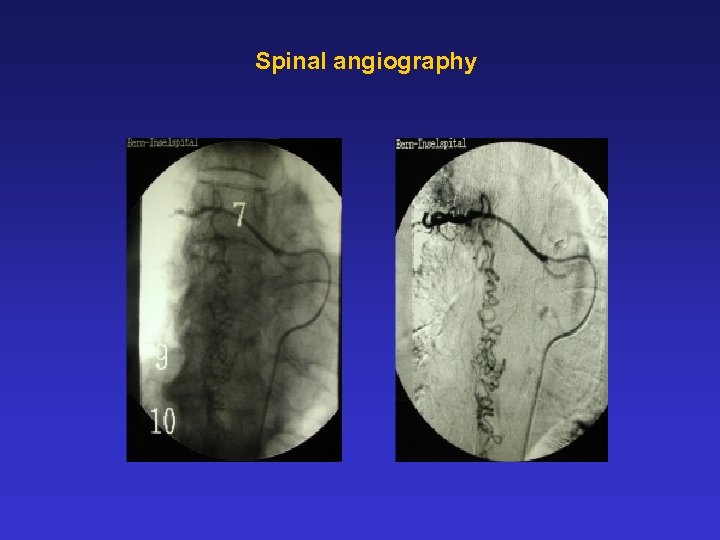

Spinal angiography Spinal angiography